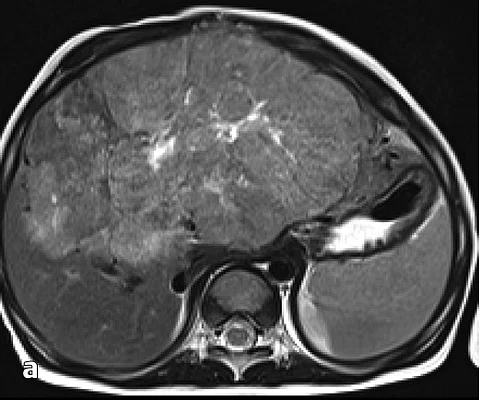

Ein 42-jähriger Patient hat vor 6 Monaten eine radikale Prostatektomie aufgrund eines Prostatakarzinoms (Gleason 3+4, Stadium pT2) erhalten. Nun stellt er sich mit einer Schwellung am linken Hoden vor.

Die physikalische Untersuchung offenbarte mehrere feste bis harte, gleichzeitig irregulär weiche Massen im linken Skrotum. Die Massen waren 1cm bis 3cm groß.